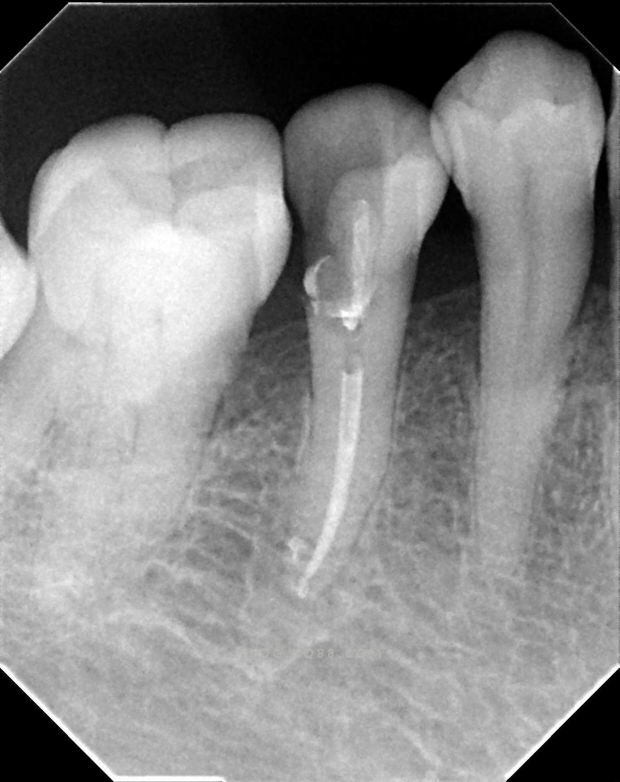

牙髓的血液来源于上、下牙槽动脉。动脉经根尖孔进入牙髓后,在牙髓中央区向冠部行走,沿途向周边发出分支,从小动脉到微动脉,最后形成毛细血管。毛细血管存在于整个牙髓,并在成牙本质细胞下层形成了密集的毛细血管网,以满足邻近成牙本质细胞层和多细胞层内细胞的功能需要。流经毛细血管的血液回流到毛细血管后静脉和小静脉,出根尖孔后汇入牙槽静脉。多根牙在牙髓室内有丰富的血管吻合,但由于来源于副根管的交通血管不足或缺乏,牙髓无有效的侧支循环。